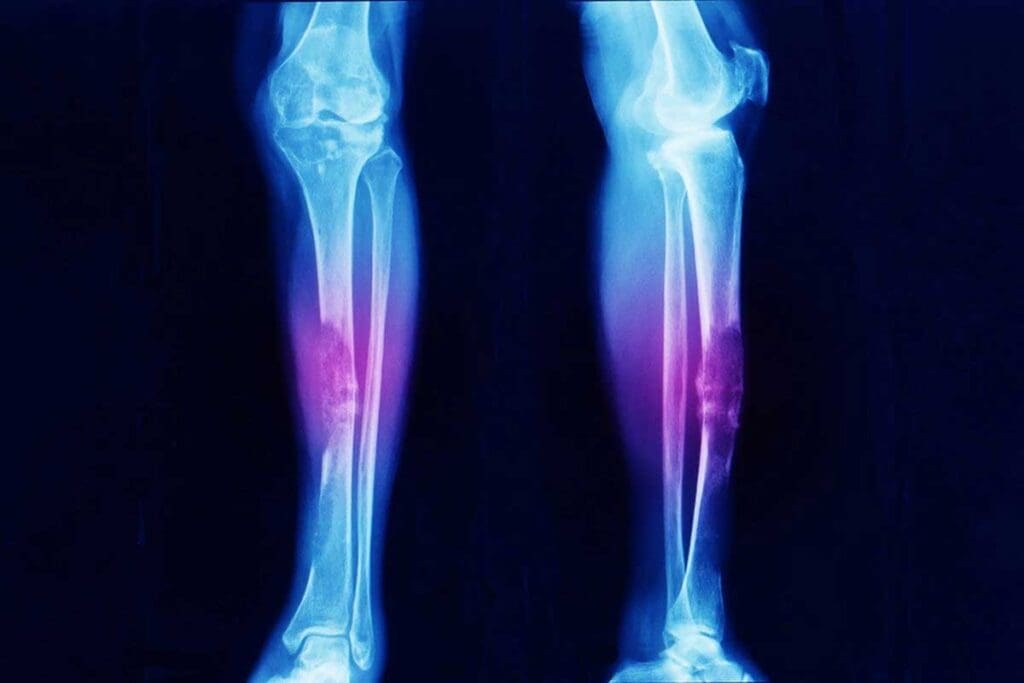

Imaging Studies

Imaging studies are key in diagnosing Ewing sarcoma. X-rays, Magnetic Resonance Imaging (MRI), and Positron Emission Tomography (PET) scans are used. MRI is great for seeing how big the tumor is and where it is.